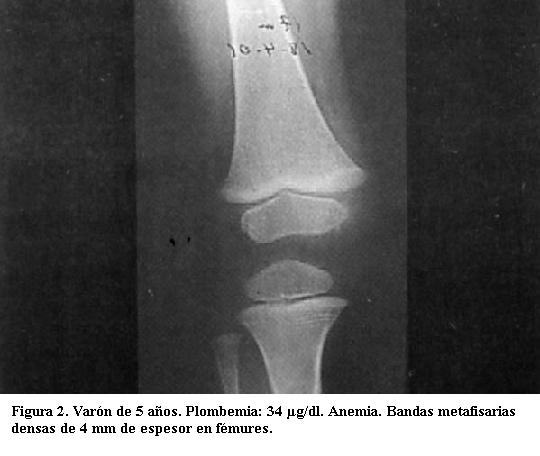

Son visibles radiológicamente cuando la absorción del tóxico se ha mantenido durante varios meses (figuras 1 y 2) (4).

Tienen varios milímetros de espesor y sus límites son nítidos. Son tanto más densas cuanto mayor sea el grado de absorción del metal y tanto más anchas cuanto más haya durado el proceso de absorción (figuras 3, 4 y 5) (5).

Predominan en las de crecimiento más rápido (las ubicadas en rodillas y muñecas) incluido el peroné, signo de importancia ya que otras enfermedades que producen bandas densas metafisarias no afectan este hueso (3).